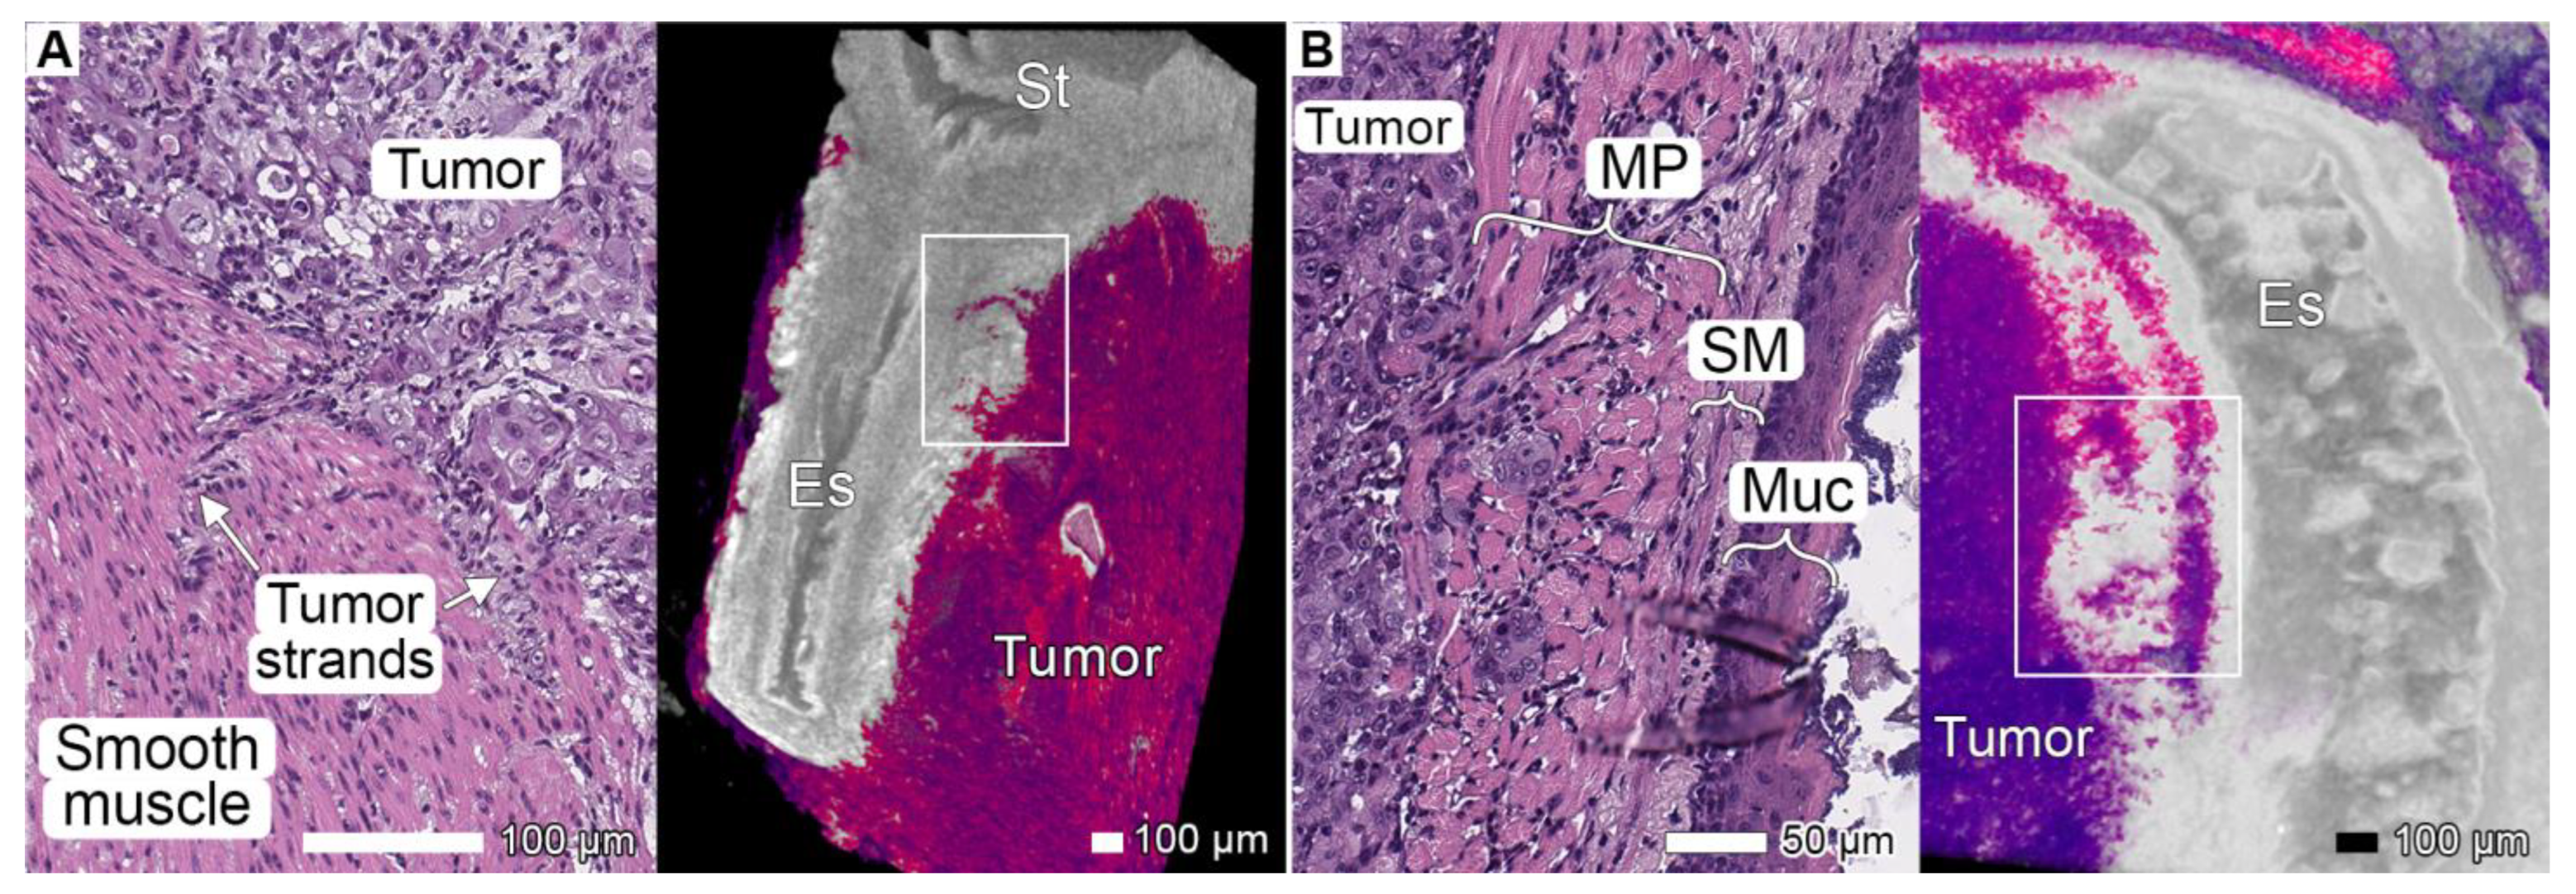

3.2. Tumor Invasion into the Esophagus and Stomach